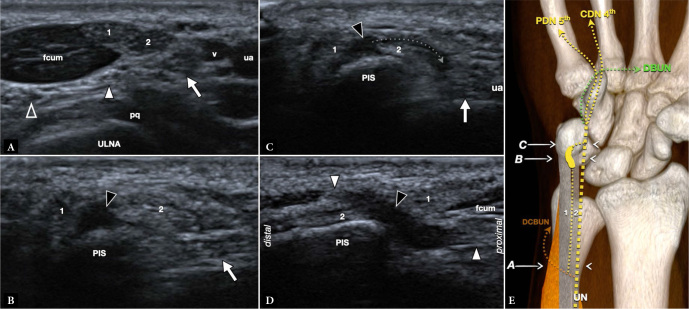

Results: Between October 2019 and October 2023, six cases were found in five patients, where ultrasound demonstrated previously undescribed-at-imaging anatomical variations of the distal ulnar nerve on six distal forearms. The variant was symptomatic in three cases in which possible distal compression was clinically suspected. A branch of the ulnar nerve made a loop around the flexor carpi ulnaris, which also presented with a variation of normal anatomy. In symptomatic patients, the diameter of the aberrant branch (retrospectively measured) was significantly enlarged.

Conclusions: High-resolution ultrasound can accurately demonstrate ulnar nerve variants even when only small nerve fascicles are involved, which may be clinically relevant and misinterpreted. Loops of the ulnar nerve are rare, but likely under-recognized. We think that symptoms are generally tolerated by patients if the motor branch of the ulnar nerve is not affected, as in our cases.